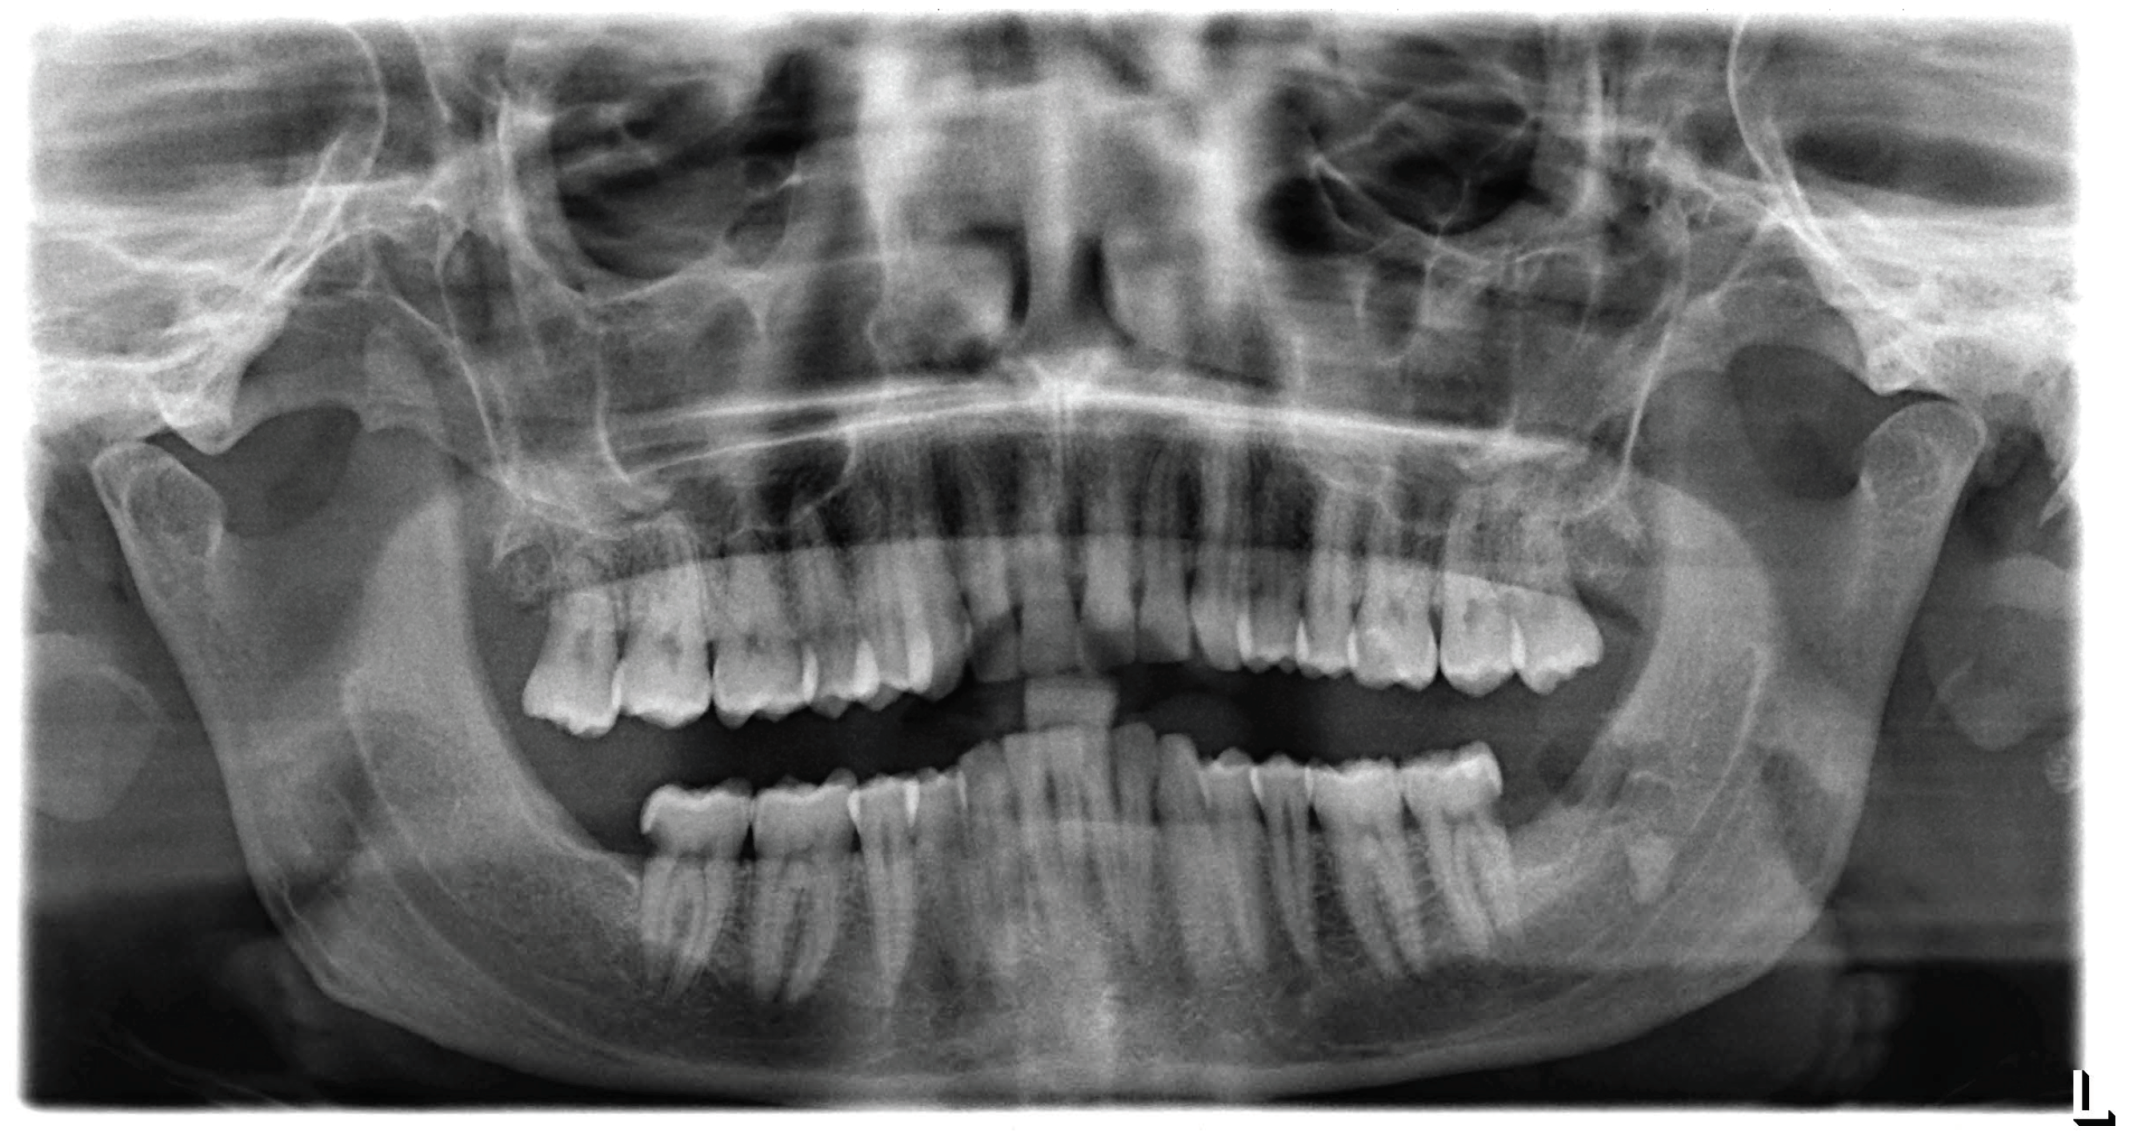

The patient showed up to our clinic with complaints following a wisdom tooth extraction. Periapical and panoramic radiographs (Figure 1) pointed to a mesially inclined and impacted tooth #38 having been recently extracted, which had caused caries in the distal portion of the adjacent tooth (tooth #37). A similar situation was observed on the opposite side; however, in that case, the wisdom tooth extraction had not led to any negative consequences. The extraction procedure was performed in March 2022, and lasted approximately two and a half hours. At the end of the procedure, the dentist took a post-operative dental radiograph (Figure 2) and informed the patient that a root fragment had not been removed. The dentist recommended a Cone-Beam CT scan to determine the fragment’s position. Following the dentist’s advice, the patient underwent a Cone-Beam CT scan at a medical center in March. On the same day, the patient returned to the dentist with the results, which showed that the root fragment had been displaced into the submandibular space (Figure 3), further necessitating a removal procedure at a hospital facility. The patient reported undergoing antibiotic and anti-inflammatory therapies for pain management and lowering the risk of infections prior to the surgery. In April 2022, the patient was admitted to the dentistry unit of a hospital where urgent maxillofacial surgery was deemed necessary. The patient was advised to consult a maxillofacial surgery specialist, who emphasized the importance of timely intervention to control the existing infection and prevent further complications caused by the dislocated root. Subsequently, the patient went to a private clinic, where a maxillofacial surgeon and their team performed the extraction of the dental root under both general and local anesthesia, as documented in the medical records provided to the patient. The procedure required a one-day hospital stay. Upon discharge, the patient was prescribed a supportive pharmacological therapy, including non-steroidal anti-inflammatory drugs (ibuprofen in a dosage of 400 mg every 4–6 h) and an antibiotic (amoxicillin with clavulanic acid in a dosage of 875 mg + 125 mg, twice daily for 5 days), as noted in the medical records.

Figure 1. Initial panoramic radiograph of the patient with both lower wisdom teeth mesially inclined, partially impacted, and in strict contact with the distal wall of the adjacent tooth affected by dental caries.